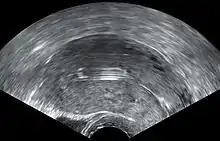

- Ovarian cysts: Enlarged follicles (ovarian cysts) have been diagnosed in about 12% of the subjects using a hormonal IUD in studies that use ultrasound to look for cysts, even if asymptomatic. In studies that only evaluate symptomatic cysts, only 4.5% of women complain of any ovarian cysts over 5 or more years of use, and only 0.3% require IUD removal for ovarian cysts.[54] Thus, any issues with ovarian cysts are not of a clinically relevant nature. Most of these follicles are asymptomatic, although some may be accompanied by pelvic pain or dyspareunia. In most cases the enlarged follicles disappear spontaneously after two to three months. Surgical intervention is not usually required.[55]